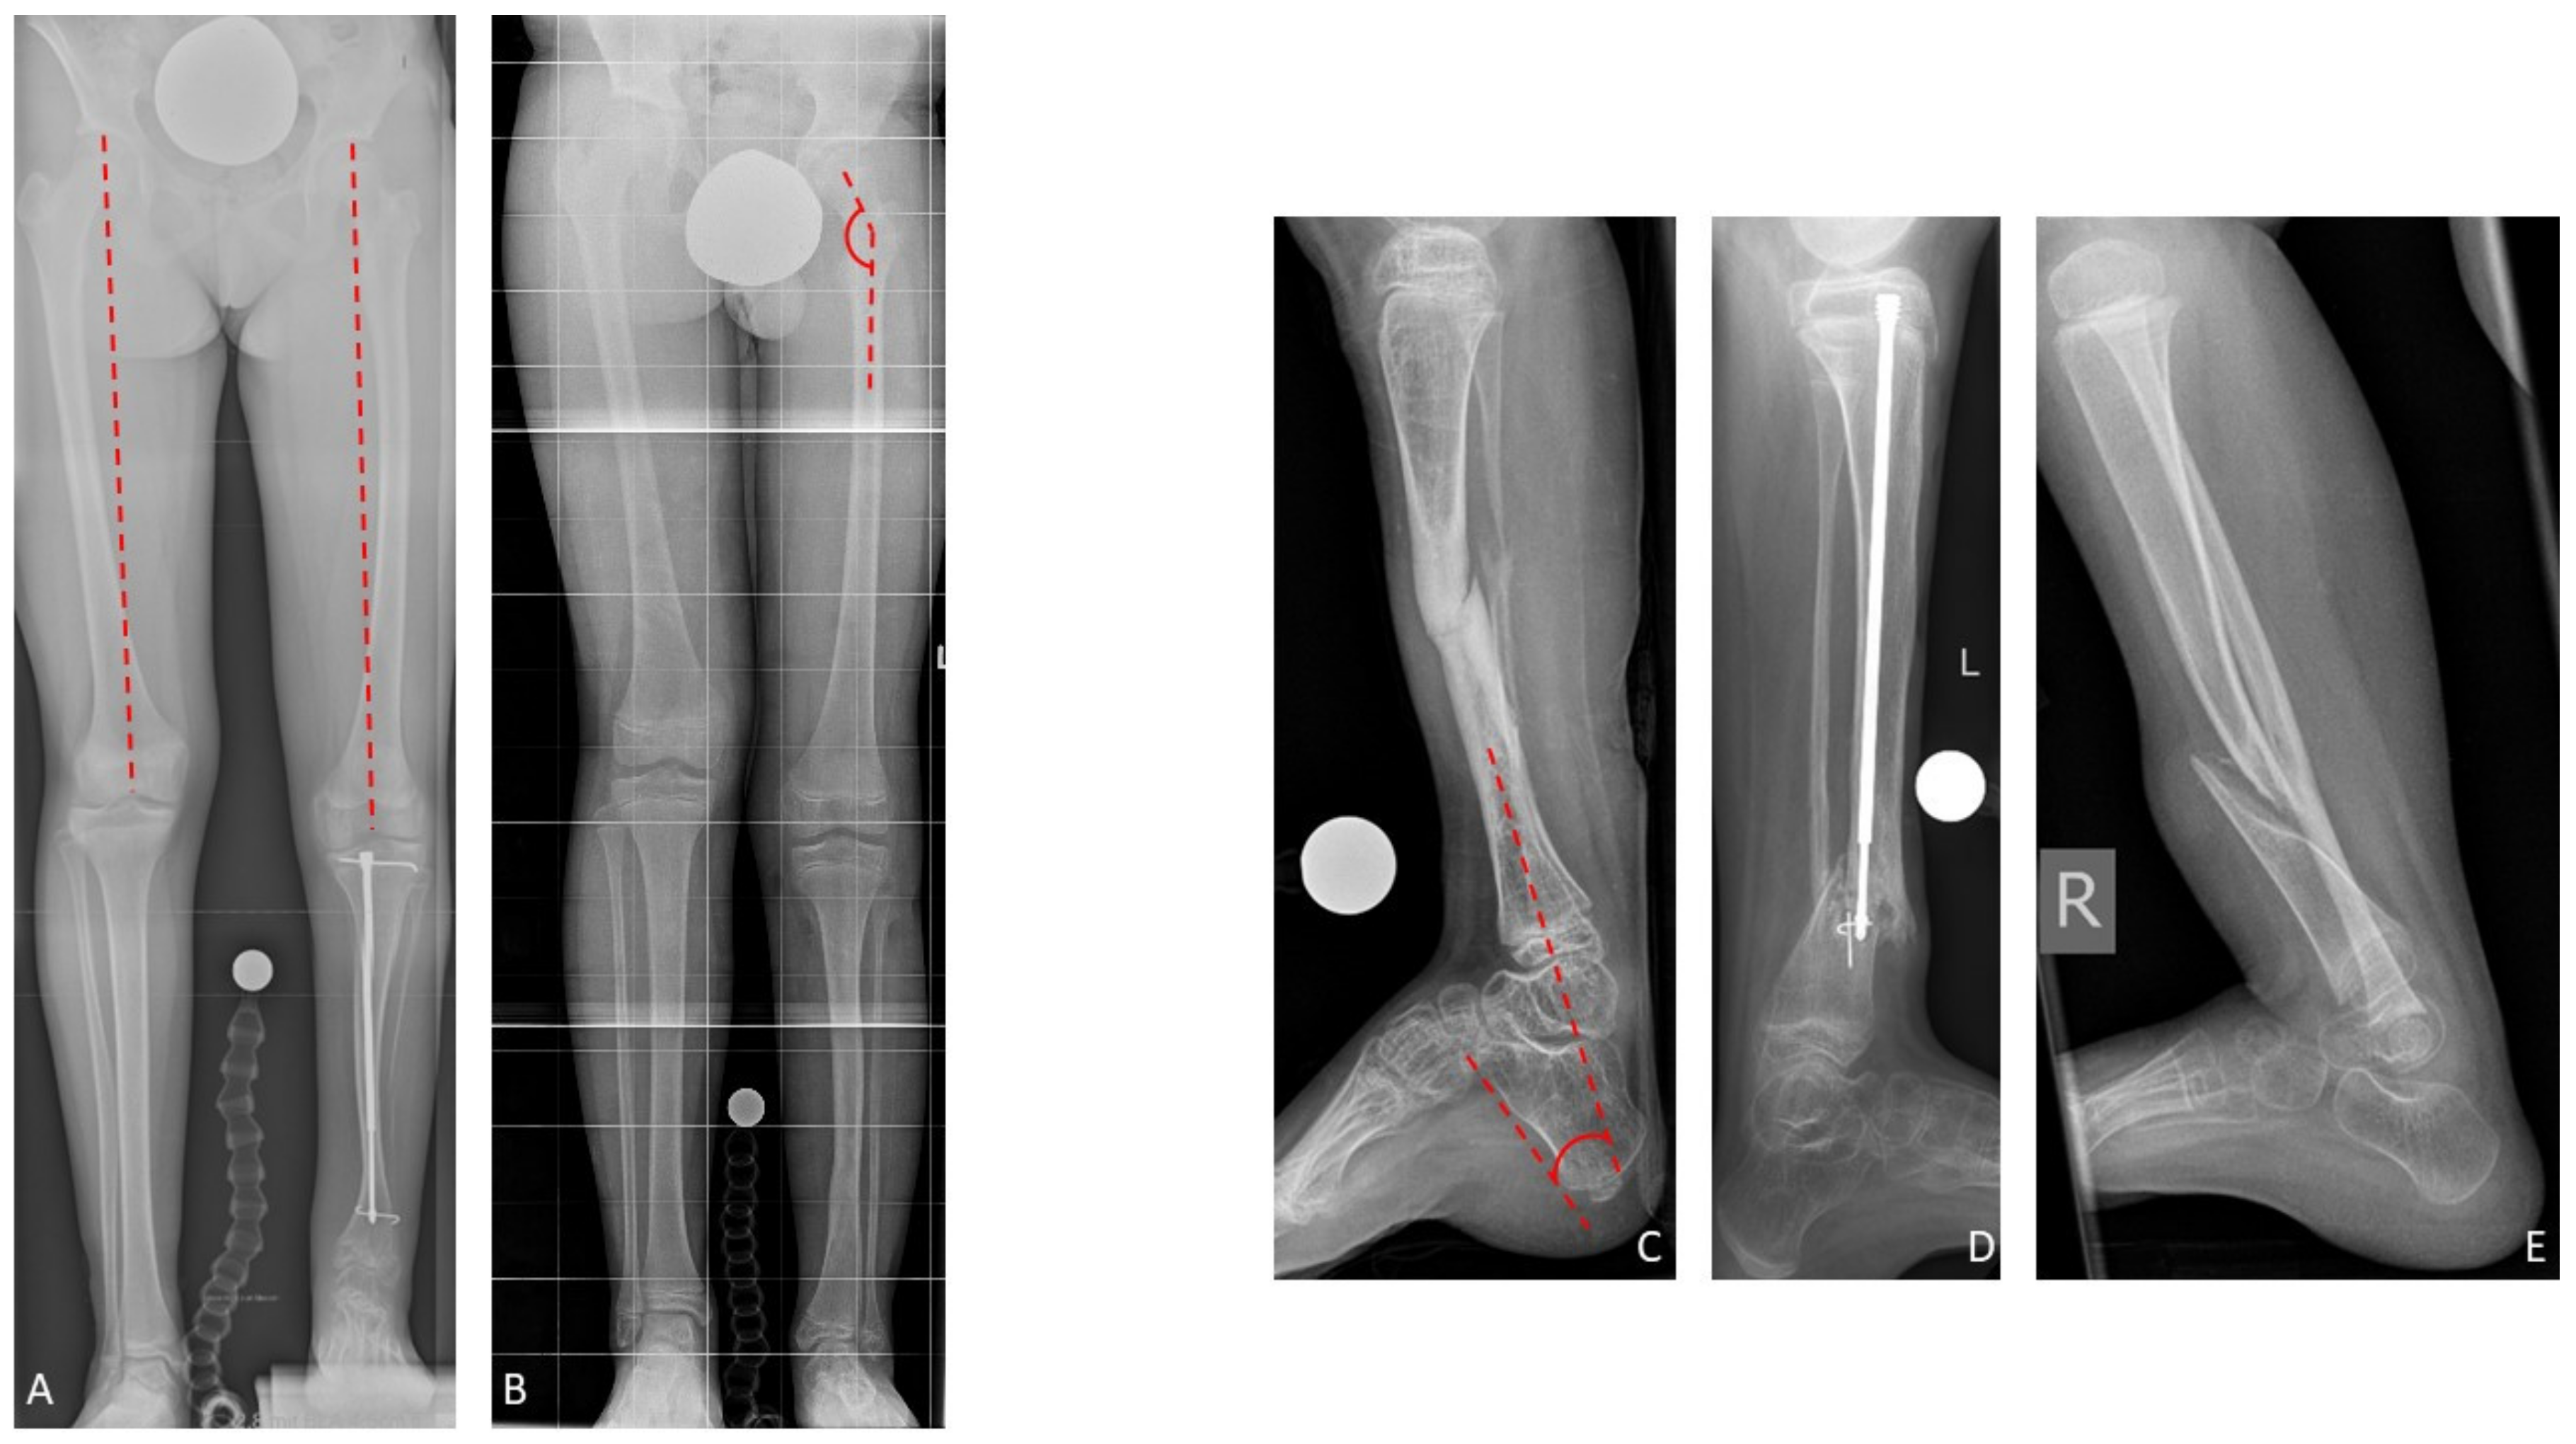

Regarding the modified Johnston criteria, seven results were grade 1, one grade 2, and seven grade 3 (Figure 7).

Figure 7. Results Group B. Fifteen-year-old male patient presenting CPT Paley type 4A with failed previous surgeries (A: a.p. view; B: lateral view). After excision of 5 cm and acute compression (C), distraction osteogenesis of 57 mm was performed (D,E). The bone regenerate showed satisfying consolidation after six months (F: red arrow: bone regenerate). Intramedullary rods were implanted when the TSFTM was removed (G). At the time of last follow-up five years after reconstruction there was no sign of refracture, but progressive ankle valgus (H: a.p. view; I: lateral view).